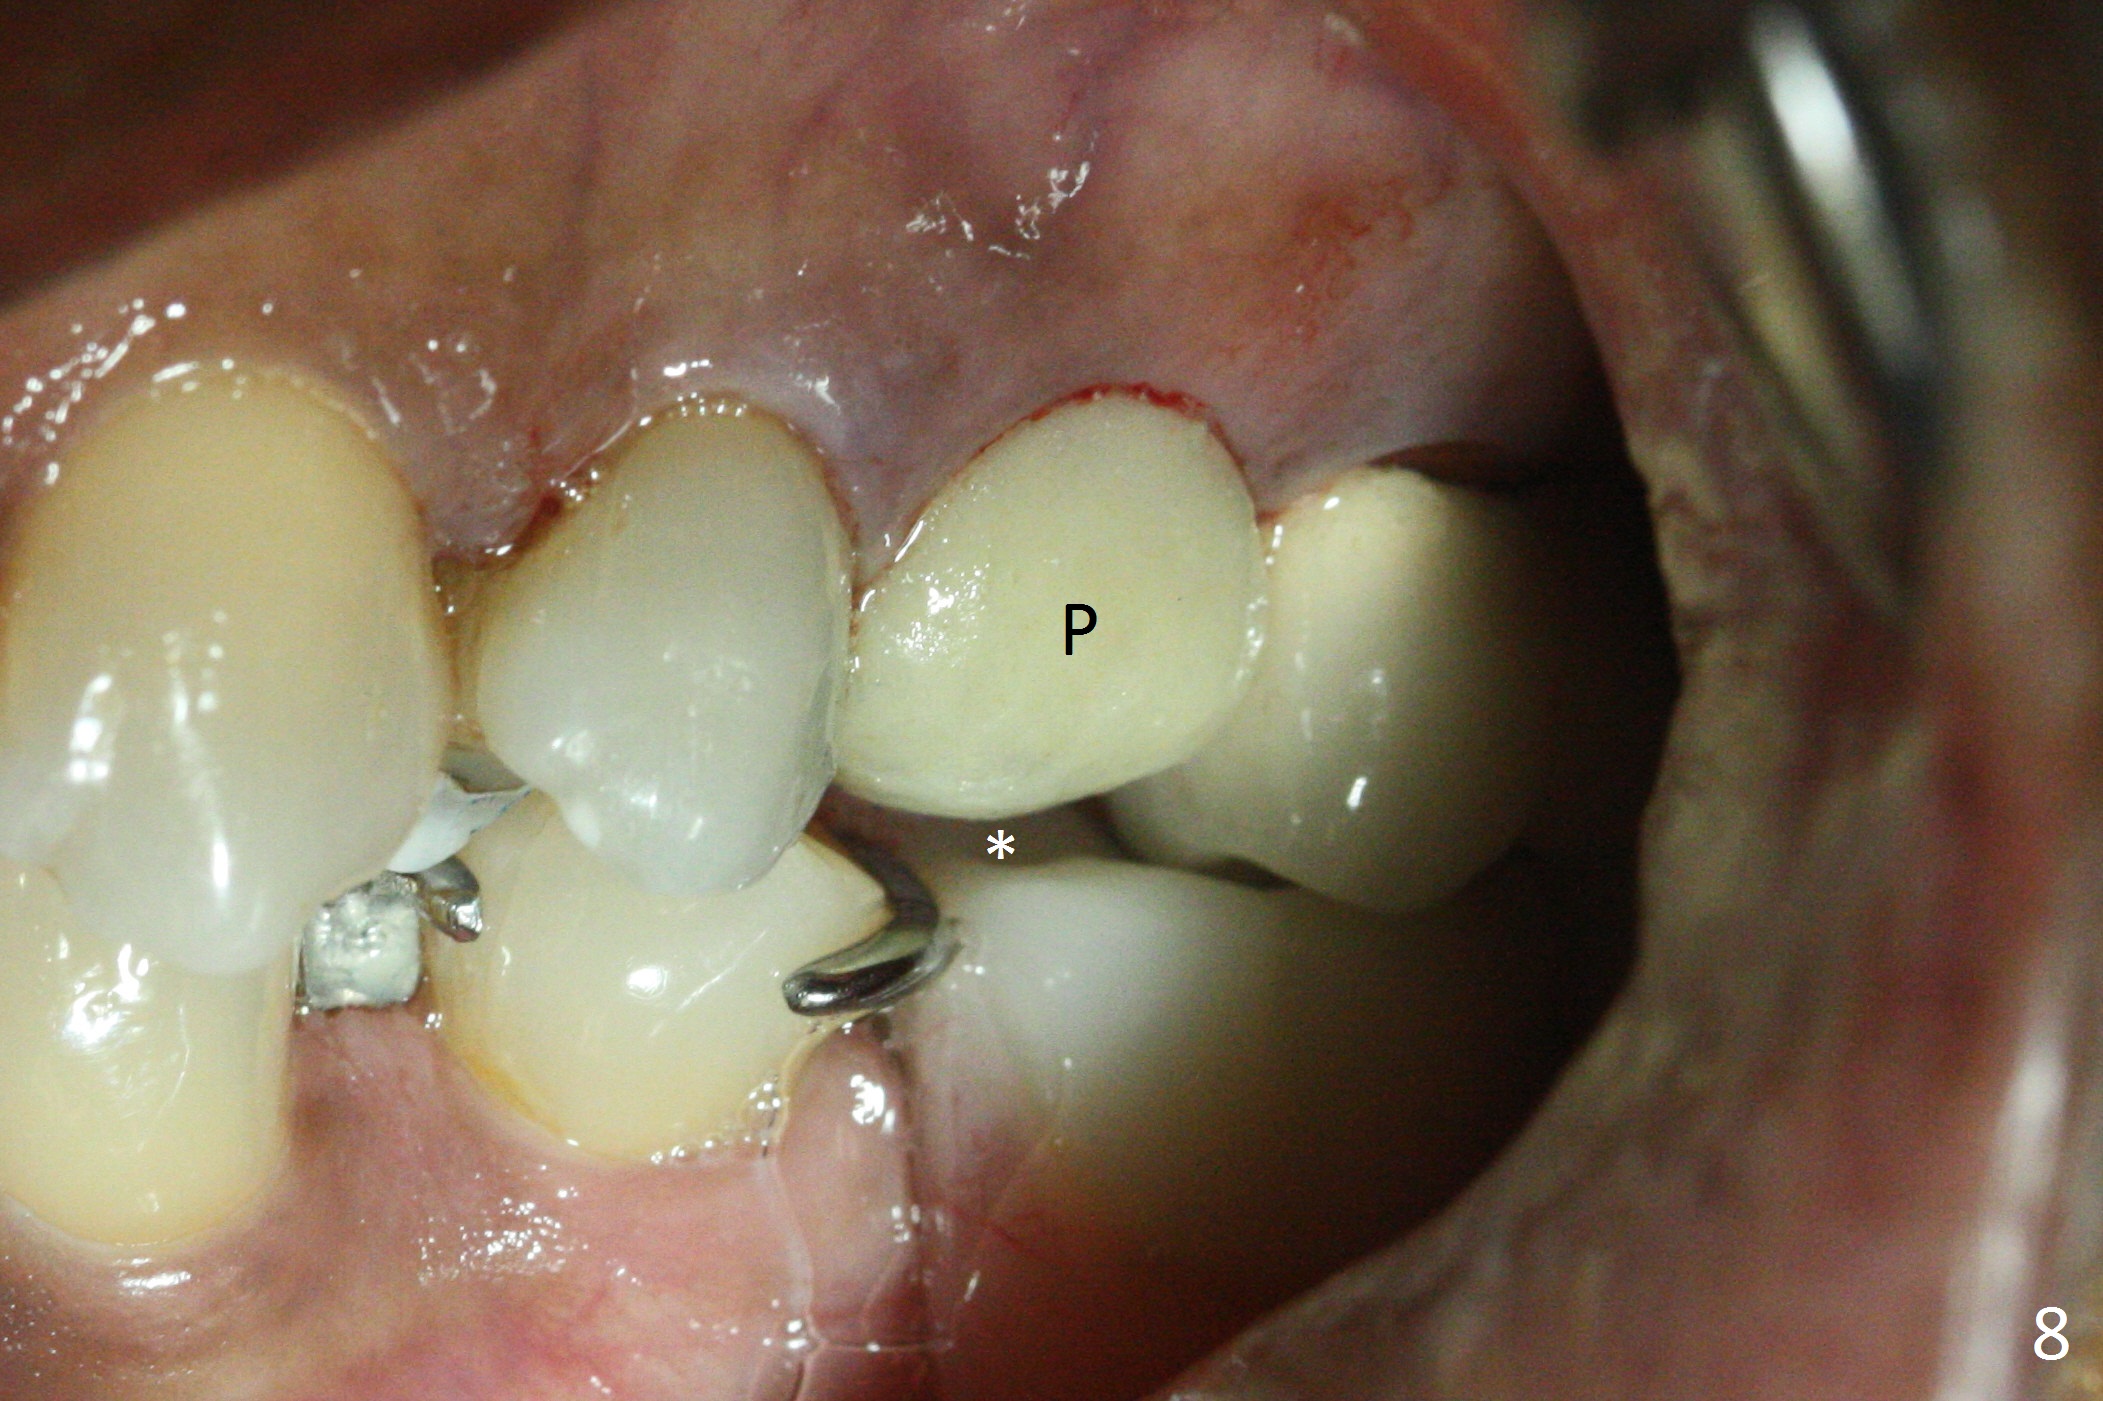

Since the apical native bone is limited at #13 after extraction, no PA is taken until a 4x11 mm dummy implant is placed after 1.6 mm and 3.3 mm drills for 13 mm (Fig.1). After using Lindamann bur to move the osteotomy distal and reusing 3.3 mm drill, the trajectory of a 4.5x11 mm IBS dummy implant improves (Fig.2,3 with low stability). When the implant is removed, the buccal portion of the socket is found to be perforated (Fig.4 P). Although the reason for the perforation is unknown, it is repaired by insertion of a piece of PRF plug, followed by allograft. #1 and 2 in Fig.4 represent the 1st and 2nd osteotomies, as shown in Fig.1 and 2, respectively. The trajectory of the final 5x13 mm implant is acceptable (Fig.5-7, different angulations), so is insertion torque (45 Ncm). After placing a 5.5x4(4) mm abutment, an immediate provisional is fabricated (Fig.8 P) with occlusal clearance (*). The interdental papillae remain in place 12 days postop (Fig.9 *). There is no sign of postop sinus infection. The provisional is loose 18 days postop; the abutment is changed to 5x4(3) mm (Fig.10). It is difficult to catch the mesial margin of the abutment for impression 4 months postop, due to poor oral hygiene and the short cuff (3 mm, Fig.11). The appointment for impression is rescheduled with emphasis on oral hygiene and no wearing the provisional for a few days prior to next appointment. Bone has grown into the space between the 1st and 2nd threads 5 months post cementation (Fig.12) and the bone is normal, solid and dense 2 years 11 months post cementation (Fig.13 >). There is mesial open margin of the tooth #14 (Fig.13,14 *).